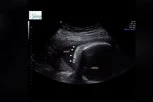

Beba Isis Eloah Ferreira Alves izazvala je pravu pažnju svojim dolaskom na svet pre vremena 2022. godine. Ova devojčica je rođena sa čak četiri bubrega - izuzetno retkom anomalijom koja se retko sreće u medicinskoj literaturi, prenosi Jam Press.

- Moja ćerka je retka i jedinstvena - rekla je Isisina majka, 21-godišnja Thalia Silva Alves, lokalnim medijima. Lekari su shvatili da Isis ima problem sa bubrezima dok je bila u stomaku, ali nisu bili sigurni o čemu je reč. Tek kada je Isis imala pet meseci i bila podvrgnuta hirurškoj intervenciji, lekari su potvrdili da ona zapravo ima ne jedan, već dva dodatna bubrega.